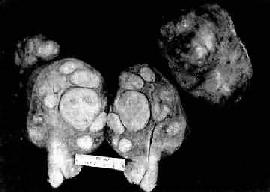

肉眼观,分弥漫型及局限型两种。弥漫型的子宫内膜呈弥漫增厚,不规则形、息肉或菜花状,质脆,常见出血、坏死或溃疡形成。组织浸润肌层,深浅不一(图13-8)。局限型多位于宫底或宫角,后壁多于前壁,常呈息肉状伴肌层浸润。

图13-8 子宫体腺(弥漫型)

组织弥漫浸润子宫壁,且部分突入子宫腔中形成大不不等的乳头状肿块